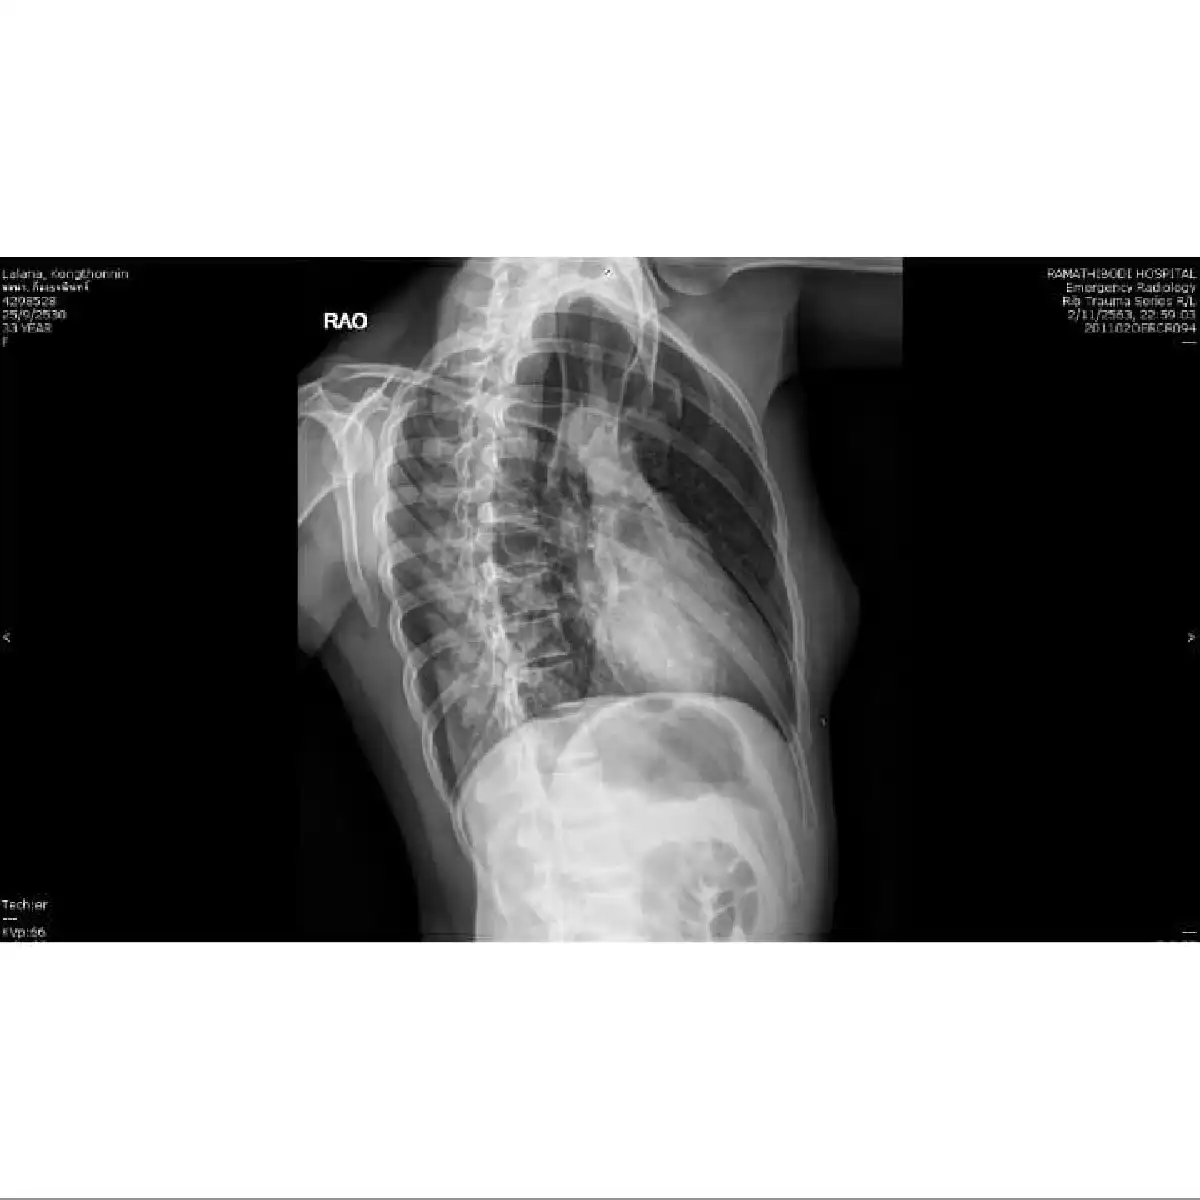

ซึ่งผลอัลตราซาวด์พบว่าอาการบาดเจ็บมาจากรอยร้าวที่กระดูกซี่โครง ทางเดียวที่จะทำให้ขึ้นชกได้คือฉีดยาชาบริเวณซี่โครงที่ร้าว เพื่อให้สามารถหายใจในสภาวะใกล้เคียงคนปกติ ไม่เจ็บเกินไป เพื่อสามารถถ่ายรายการให้ลุล่วงได้